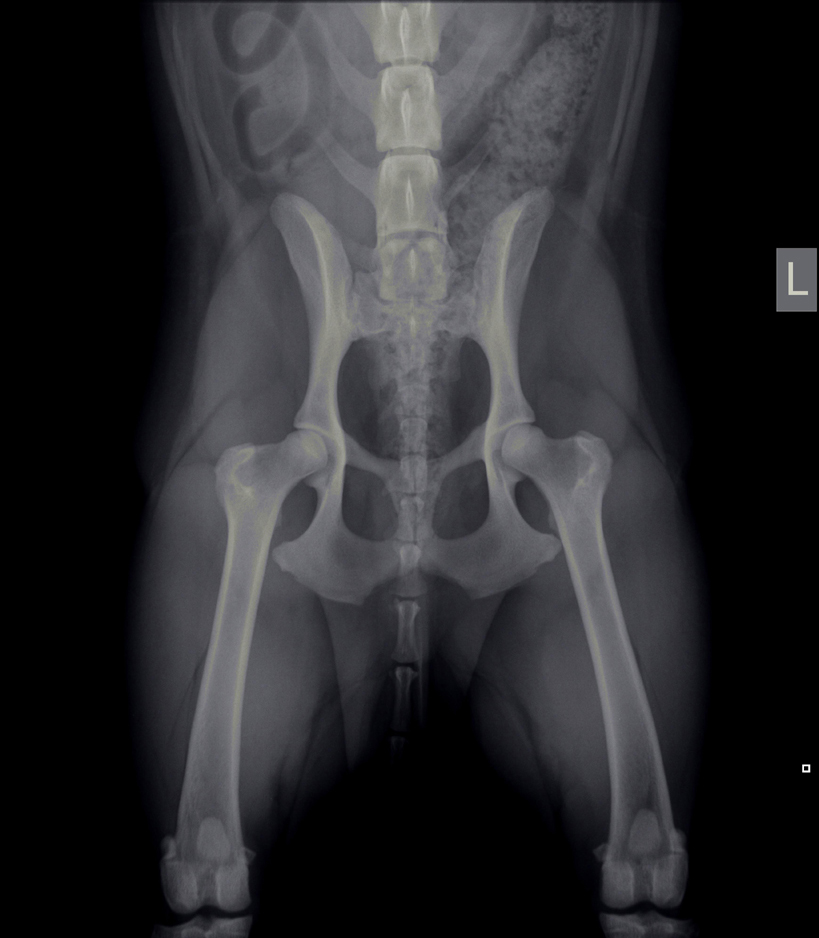

Heupdysplasie (HD)

Onder heupdysplasie wordt het volgende verstaan: een te ondiepe heupkom, waardoor de heupkop te veel ruimte heeft om te bewegen. Er is niet één enkele oorzaak voor te geven; meestal is het een combinatie van snelle groei, inspanning, voeding, leefomstandigheden en erfelijke factoren. Bij erfelijke factoren bestaat een aangeboren dysbalans tussen de spieren van het heupgewricht en de groei van bot, waardoor de heupkop niet goed in de kom wordt getrokken. Wat volgt is een abnormale ontwikkeling van het heupgewricht, wat kan leiden tot instabiliteit en daardoor irritatie van het gewrichtskapsel en het kraakbeen op de heupkop met artrose (=slijtage) als eindresultaat.

Artrose aan de heupen uit zich in het algemeen in bothaakjes aan de heupkop, verbreding van de hals van de heupkop (= de aansluiting van de heupkop met de rest van het dijbeen), onregelmatigheden in het bot van de heupkom en luxatie van de heupkop ten opzichte van de heupkom (heup geheel of gedeeltelijk uit de kom).

Met behulp van röntgenfoto’s kan de diagnose worden gesteld.

HD-foto’s en beoordeling door de Raad van Beheer

Het is mogelijk om rashonden op 12 of 18 maanden leeftijd te laten testen op heupdysplasie door het maken van röntgenfoto’s van de heupen (onder sedatie). Deze foto’s worden dan door de Raad van Beheer beoordeeld. Belangrijk is dat het stamboomnummer van het dier bekend is, evenals het chipnummer en de volledige (stamboom)naam van het dier.

HD-status

HD A (HD -)

Röntgenologisch vrij van heupdysplasie, dit betekent niet dat de hond geen drager kan zijn van de afwijking.

HD B (HD tc)

(Overgangsvorm) zijn geringe veranderingen passend bij heupdysplasie, maar die bij de fokkerij niet van belang te zijn.

HD C (HD ±)

(Licht positief) duidelijke veranderingen, passend bij het ziektebeeld van heupdysplasie.

HD D (HD +)

(Positief) duidelijke veranderingen, passend bij het ziektebeeld van heupdysplasie.

HD E (HD ++)

(Positief in optima forma) ernstige misvormingen van het heupgewricht.

De afwijkingen die op de röntgenfoto’s te zien zijn, komen niet altijd overeen met de last die de hond van deze aandoening heeft. Honden met aanmerkelijke afwijkingen zijn soms klachtenvrij, terwijl andere honden, met flinke pijn- of bewegingsklachten, soms slechts een beperkte afwijking op de röntgenfoto’s laat zien.